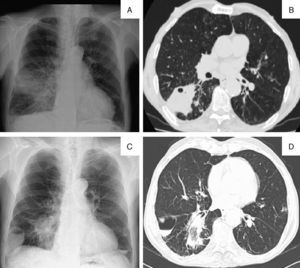

Un varón de 70 años de edad, fumador y sin antecedentes médicos de interés, fue ingresado en el servicio de neumología por presentar disnea de esfuerzo moderada, asociada a fatiga de 3 meses de evolución. El paciente refería tos productiva con expectoración mucosa y negaba haber presentado hemoptisis y sintomatología general. La auscultación pulmonar objetivó una disminución de los sonidos respiratorios en el lado derecho. La analítica de sangre mostró una elevación de los marcadores inflamatorios sistémicos. La radiografía de tórax (fig. 1A) reveló una opacidad en el pulmón derecho asociada a un patrón micronodular. La tomografía computarizada (TC) torácica (fig. 1B) mostraba una consolidación en el lóbulo inferior derecho (LID) con cavitación inicial. En la broncoscopia no se observaron lesiones endobronquiales, y el estudio microbiológico del aspirado solamente reveló un Staphylococcus aureus resistente a meticilina. A pesar de la antibioterapia dirigida, la evolución clínica y radiológica no fue favorable y la radiografía de tórax (fig. 1C) mostró una opacidad y una nueva lesión cavitaria; la TC torácica (fig. 1D) confirmó la presencia de una consolidación con una cavitación, y una formación quística compatible con un neumatocele. Se efectuó una biopsia de la lesión parenquimatosa que fue compatible con neumonía organizada (que se trató con 0,75mg/kg/día de prednisona durante 4 semanas, con posterior reducción gradual de la dosis), con buena evolución clínica y radiológica. Durante el seguimiento se observó la resolución de la lesión del neumatocele.

A) Radiografía de tórax inicial en proyección posteroanterior (PA): opacidad heterogénea en el pulmón derecho asociada a un patrón micronodular. B) Tomografía computarizada torácica inicial en plano axial (axial plane [AP]): consolidación en el segmento apical del lóbulo inferior derecho con cavitación inicial. C) Radiografía de tórax en proyección PA: opacidad triangular y nueva lesión cavitaria con nivel hidroaéreo, que ocupaba el ángulo costofrénico derecho. D) Tomografía computarizada torácica en AP: consolidación con cavitación en el segmento apical del lóbulo inferior derecho y formación quística con nivel hidroaéreo, compatible con neumatocele.